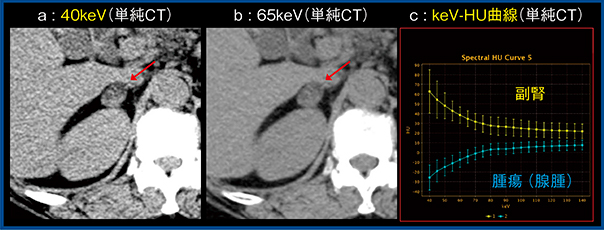

また,仮想単色X線画像のエネルギーレベル(keV)を横軸,CT値(HU)を縦軸としてプロットしたkeV-HU曲線は,物質ごとに固有のパターンを示す。副腎腺腫の症例(図4)では,腫瘍(←)の部分に関心領域(ROI)を設定すると,keV-HU曲線は低エネルギーになるほどCT値が低下し(青線),脂肪に特徴的な曲線パターンを呈することから,lipid richな副腎腺腫と容易に診断できる。同曲線解析を行わなくても,低keVで正常副腎と腫瘍とのCT値差が大きくなっているため,エネルギーを変化させるだけで脂肪を含む腫瘍であると判断できる。

このように,DECTでは,さまざまなエネルギーにおけるCT値の変化から組織の違いを推測可能であり,CT値の上昇が急峻であれば,細胞密度の高い腫瘍と推測できると考える。

図4 keV-HU曲線に基づく副腎腺腫の診断1)